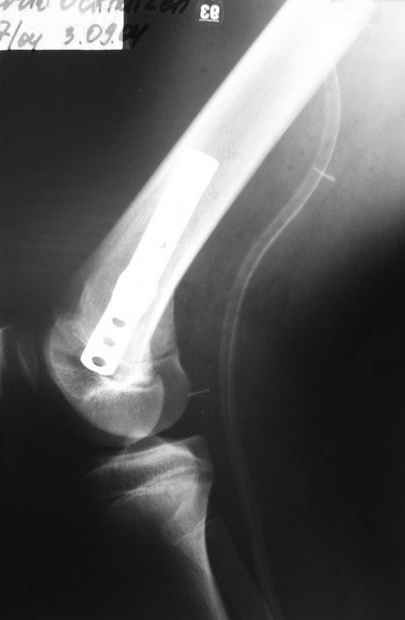

Как вариант решения прогрессирующей вальгусной деформации коленного сустава я бы предложил косую остеотомию дистального отдела бедра с фиксацией пластиной и компрессирующим винтом.

Взгляните на снимки , может быть это вам поможет.

Около 5 лет применяю этот тип дистальной остеотомии бедра для коррекции механической оси Н/К ( более 20 случаев) - достаточно эффективная операция.

- Конечно, другая: я применял этот тип остеотомии при различных состояниях, приводящих к деформации механической оси сустава, но техника её тандартна,

расчеты индивидуальные.

-Деформация оси сустава может быть варусной или вальгусной, причины - структурные изменения в латеральном -или медиальном отделе сустава (переломы, патология зон роста, дисплазии, дегенеративные процессы) результат лечения внутри- или внесуставного перелома и восстановление оси обуславливается анатомичностью репозиции и адекватностью фиксации. Нередко в запущенных -неправильно срасшихся unicompartmental внутрисуставных переломах восстановление оси и опороспособности достигается периартикулярными

остеотомиями...

- *как разбитую чашку не клей - все равно новой она уже не станет*, - поэтому при подтверждении некроза мыщелка бедра в сочетании с деструкцией тибиального плато, артропластика остаётся единственной альтернативой для восстановления функции и опорности ноги.